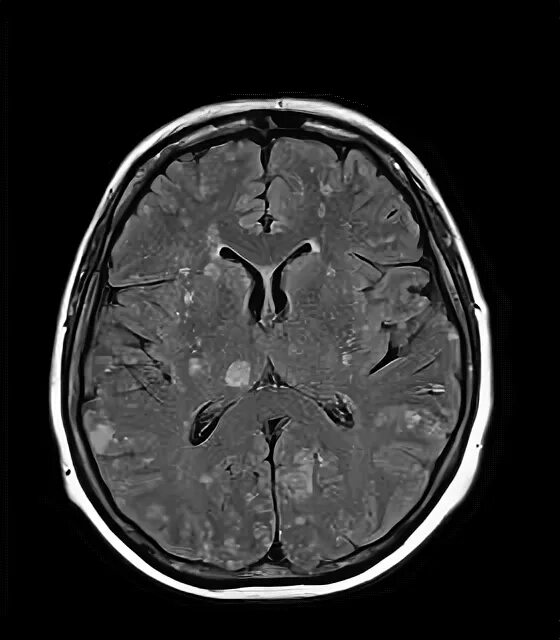

Отек мозга метастазы